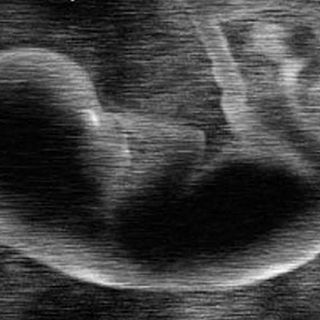

C-sections are a major surgery, one that involves cutting through the abdominal wall, tearing abdoninal muscles apart to expose the uterus, and then cutting through the wall of the uterus. As a result, recovery is like any from a major surgery, something that many people forget because of how common C-sections are. The good news is that because C-sections are so routine, they are extremely safe. However, proper care for the wound post-op is essential.

During a C-section, doctors cut through several layers of different tissue; after the baby comes out, the uterus will be closed with dissolveable stitches, while the abdominal tissue may be glued or stapled shut. (Depending on how the wound was closed, you may receive specific instructions about how to handle that type of wound recovery.) When the surgery is completed, hospital staff will cover the wound with an adhesive bandage that holds the skin in place. In most hospitals, this bandage will be changed before you leave the hospital. You will be instructed when to remove the bandage you’ve worn home. Usually, you will be told to bathe with the bandage and leave it on for a few weeks, so the skin underneath can heal before it is exposed to anything that might get into your bloodstream and cause a serious infection. Once this bandage comes off after a few weeks, the wound is superficially closed, and it’s harder for the would to get infected. However, at this juncture it is particularly important to care for the wound carefully, because infections can still occur.